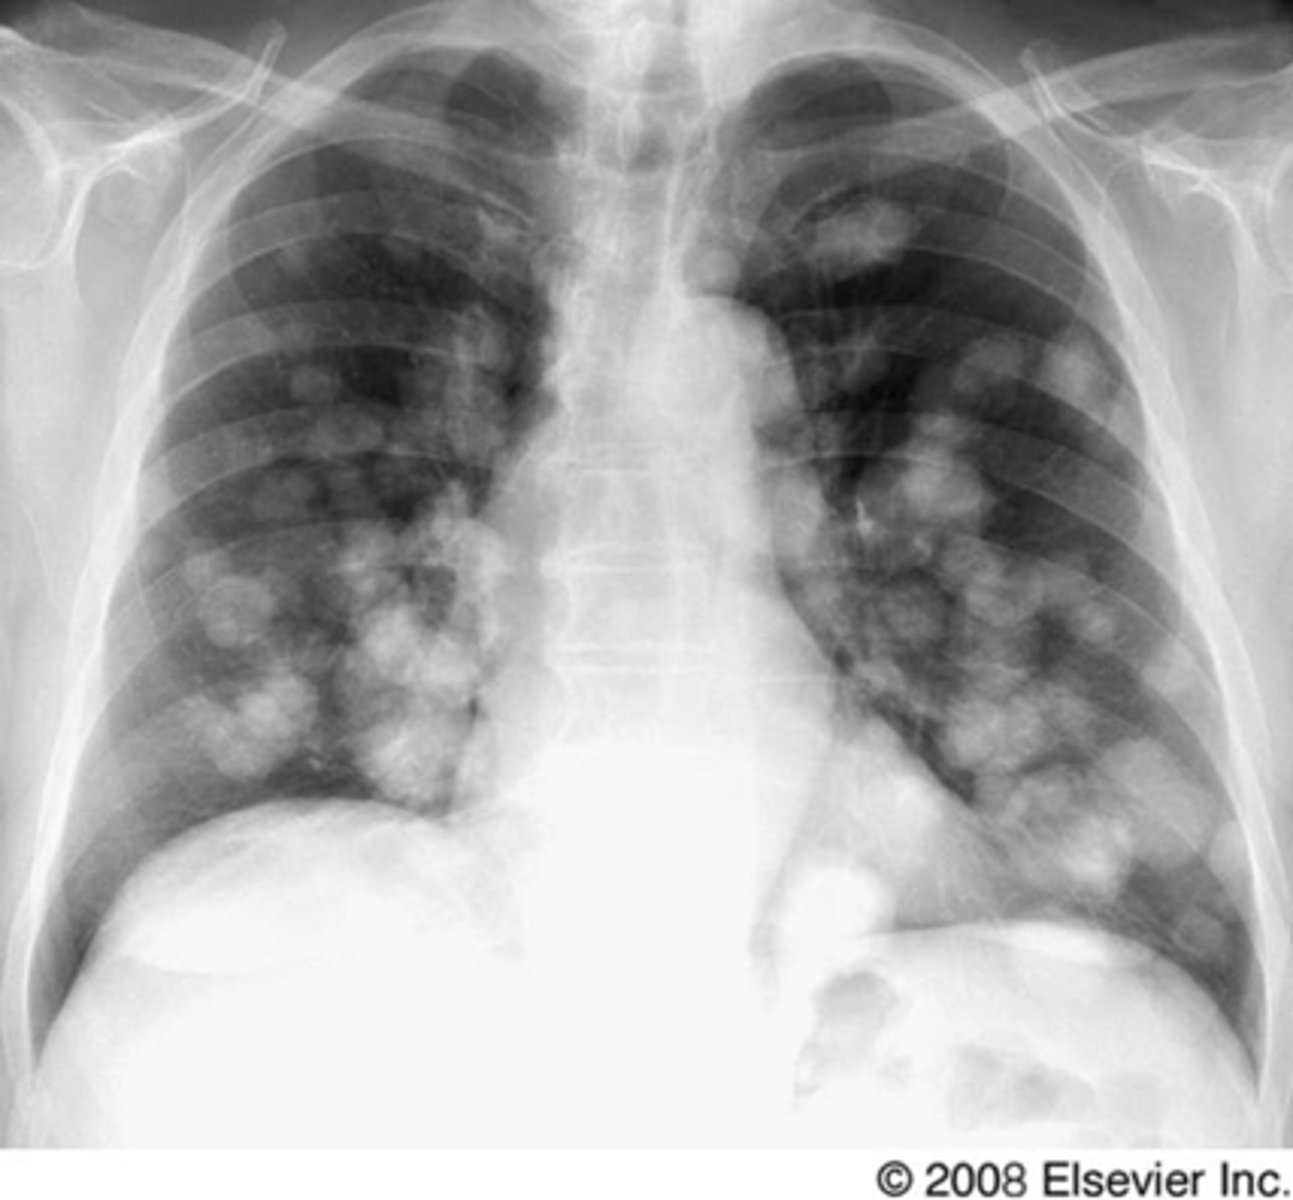

Lung cancer- metastatic disease

Multiple nodules- metastatic